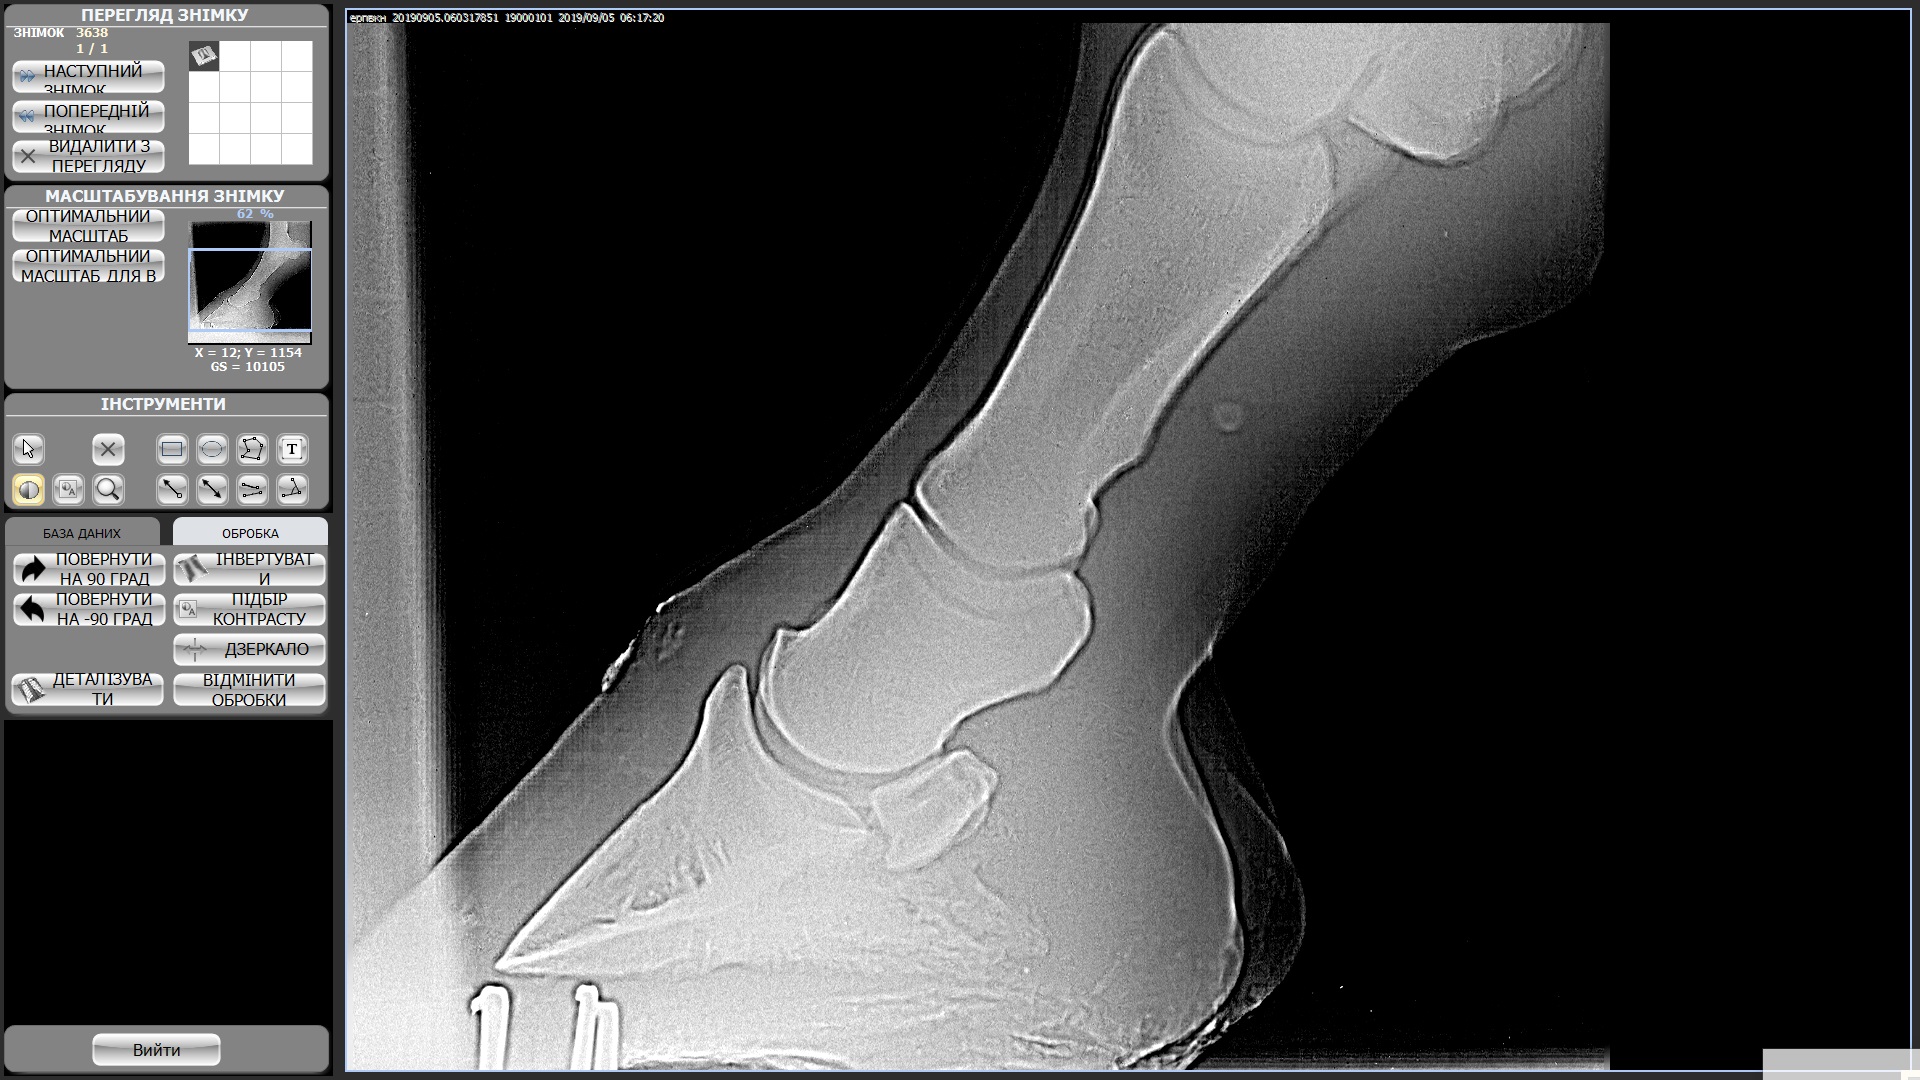

Мерин 7 лет, купили в этом году, смотрели с ветом и делали рентгены ног, прикрепила к теме. Были микротравмы суставов из за чего появляются наливы (мягкие шишки) на суставах всех 4х ног. Приглашала другого вета сказал менять постав подковами ортопедическими, так и сделали после чего конь захромал на правый перед и оба зада, проходили так неделю и сняли подковы - хромота ушла, но копытные остались налитыми, как и шишки не сошли. Вроде бы все было хорошо на протяжении 2х недель, наливы не сошли, но конь на них не жалуется. И вот на днях ходили в поля (только шагом), пару раз нас напугала то машина, то веточка и он подрывался немного. На следующее утро хромает на все 4, щупали мышцы и смотрели наливы изменений нет но конь хромает на все 4 и немного теплые копытные((((

Студдебекер 3 ЗЛ.jpg494 KB · Просмотры: 366 -

студебеккер 2 ЗП.jpg404.4 KB · Просмотры: 370 -

СтудебеккерПЛ.jpg489.8 KB · Просмотры: 327 -

Студебеккер ПП.jpg528.2 KB · Просмотры: 411 -